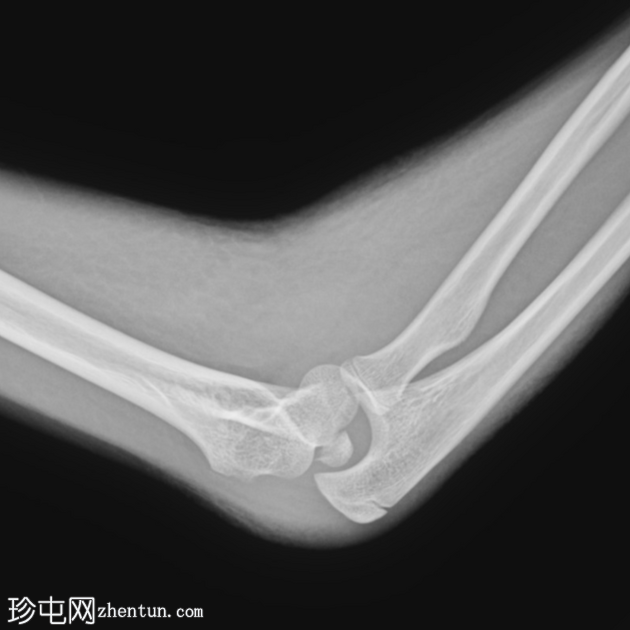

X线片

1.png

正位片

2.png

侧位片

关节对位不良。桡骨和尺骨外侧脱位。

肘关节内可见骨碎片(正位/侧位片)。

肘关节积液(帆状征)。

桡骨头附近可见碎裂性骨折。